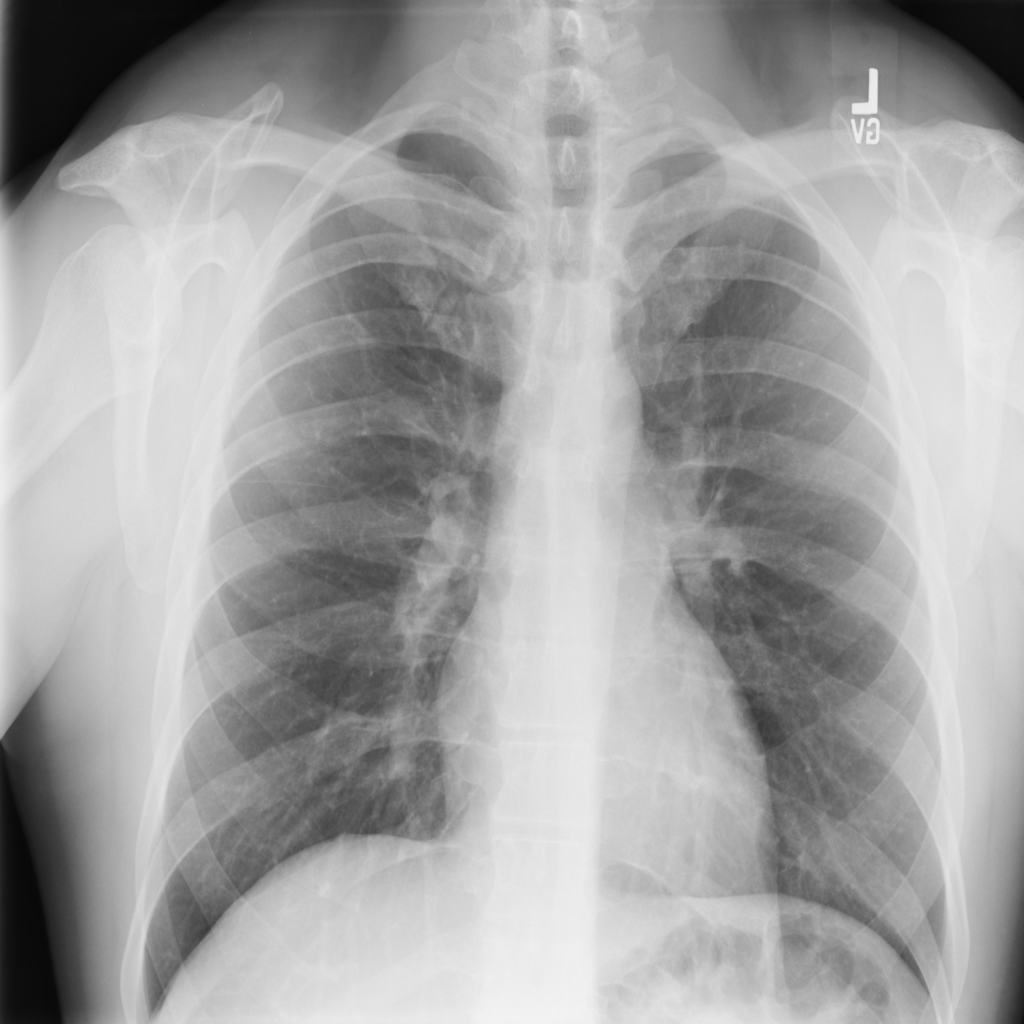

PAT-1F50 · IMG-000Fibrosis

PAT-1F50 · IMG-000

PA